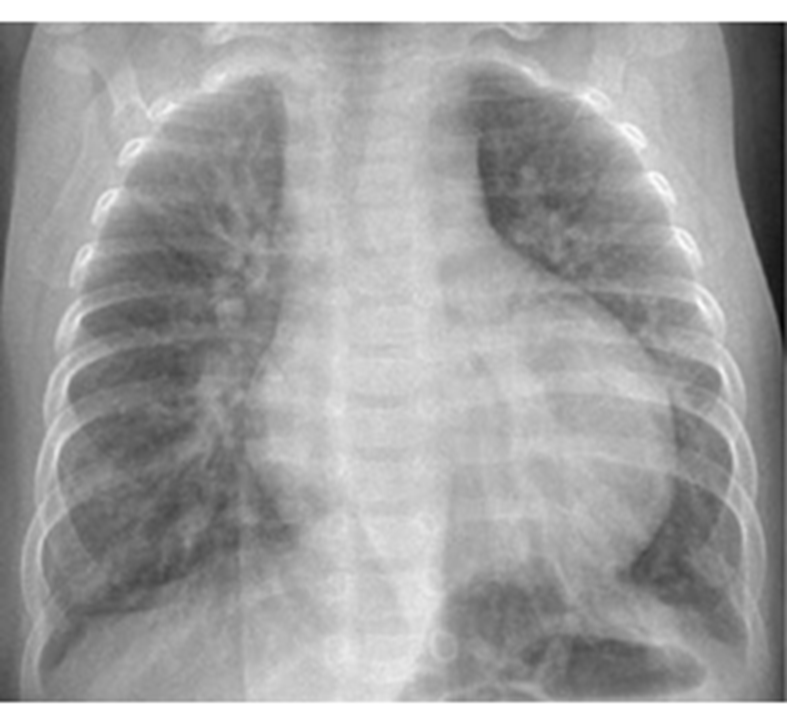

Chest X-Ray Findings

Cardiomegaly and plethoric lungs (increased pulmonary blood flow from left-to-right shunts).

Signs of Plethoric Lungs

Plethoric lung fields are indicative of increased pulmonary blood flow (perfusion) and are seen in left-to-right shunts.

Plain radiograph: prominent pulmonary vasculature.

Dilated and tortuous pulmonary vessels extend further into the peripheral one-thirds of the lungs

Diameter of a pulmonary artery is greater than the accompanying bronchus